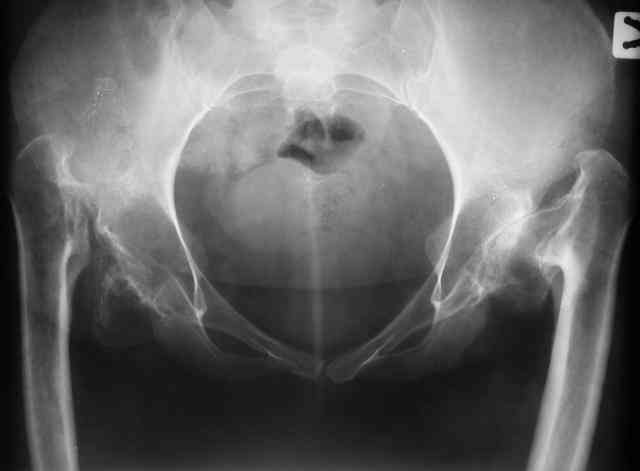

Уважаемые коллеги! В клинику обратилась больная 30 лет с жалобами на боль в области тазобедренных суставов (больше справа), ограничение движений в них.

Дисплазия была выявлена в 3-летнем возрасте, от операции родители тогда отказались. Около года назад при подъеме с кресла почувствовала резкую боль и хруст в правом бедре. С тех пор ходит только с ходунками. Выражены сгибательно-приводящие контрактуры. Справа - положительный симптом прилипшей пятки.

Мы планируем двустороннее тотальное бесцементное эндопротезирование. Первый этап - правый сустав. Чашку планируем имплантировать на свое анатомическое место, для чего резецируем часть бедренной кости. Смущают сильный остеопороз в области впадины и кривизна бедра... Ваши комментарии? -- С уважением, А. В. Вакуленко